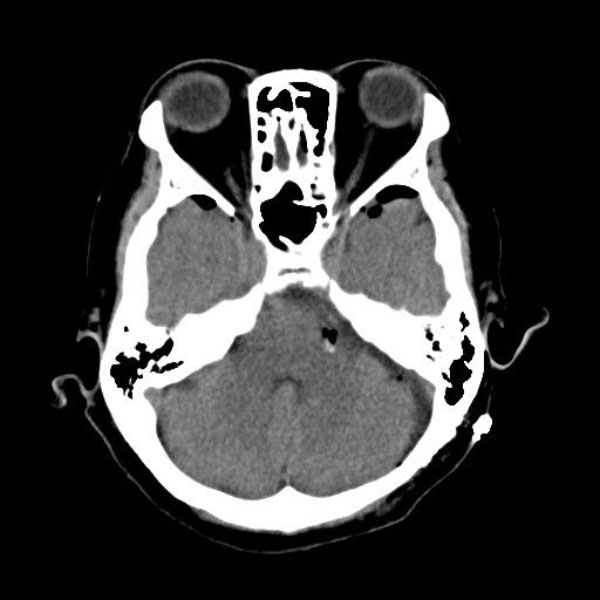

症例 '25年10月

No.

558

当院外来

'25年10月

60代

左顔面痙攣

(痙攣をとること)

手術前

減圧前

減圧後

術後血管撮影